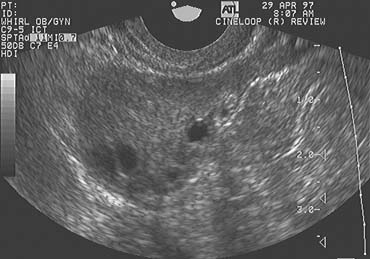

Color Doppler imaging, combined with high-resolution grayscale ultrasonography, provides the means to critically evaluate corpus luteum development and function (Fig. 5). Color Doppler imaging reveals blood flow in the microvasculature that cannot be seen with conventional grayscale imaging and spectral Doppler interrogation generates flow velocity waveforms that may then be analyzed. After corpus luteum regression, the corpus albicans remains visible, at least up until the time of the next ovulation (Fig. 6). Several such structures may occasionally be observed within the ovaries, depending on the proximity of newly emerging small follicles.

Fig. 6. Corpus albicans. The corpus albicans is well-circumscribed by a ring of hyperechoic tissue on the left side of the image of the ovary. This image was recorded on the day before ovulation in the subsequent menstrual cycle.